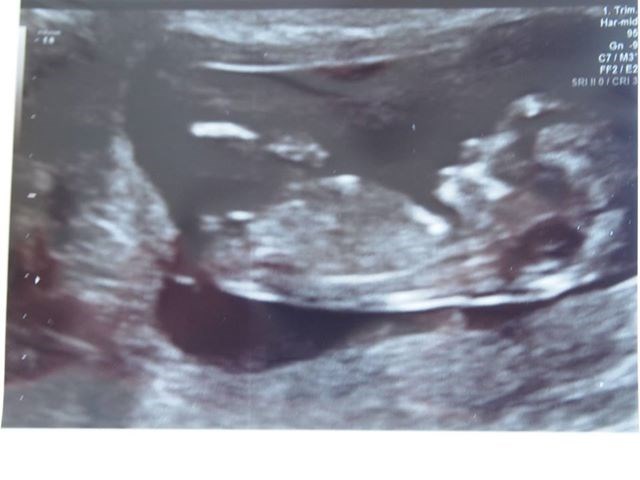

I fredags blev det endelig tid til at vi skulle til nakkefoldsscanning. Jeg havde glædet mig meget, men onsdag og torsdag aften spekulerede jeg som en gal. Jeg har haft en del kvalme og har stadig lidt, hvis jeg bliver sulten eller træt, men da man jo ikke har mærket barnet endnu, blev jeg pludselig nervøs over, om der overhovedet var liv derinde. Men det var der i høj grad! Der var godt nok fart over feltet hos det lille myr (måske ikke så underligt når dens søster også har krudt bagi

) Den drillede en del og ville ikke helt ligge stille, men heldigvis fangede hun den i et roligt øjeblik og kunne måle det hun skulle.

Jeg blev sat to dage tilbage og har i stedet termin den 6. marts. Skal føde på Hvidovre.

I skal ikke snydes for et billede af den lille trold, som på daværende tidspunkt målte 5,5 cm fra hoved til numse